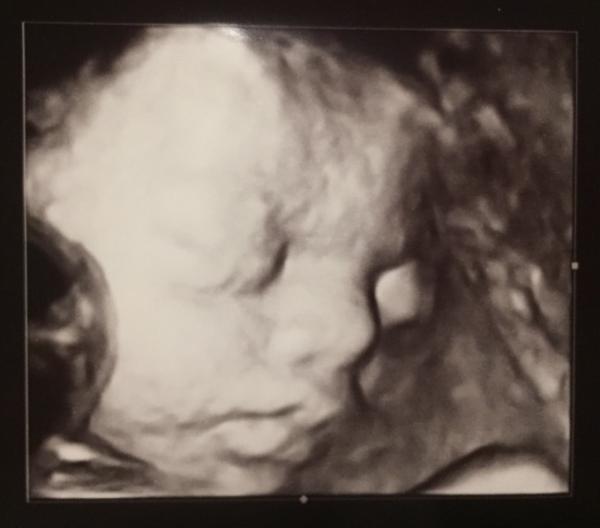

Hier noch das 2.Bild

Bild zu